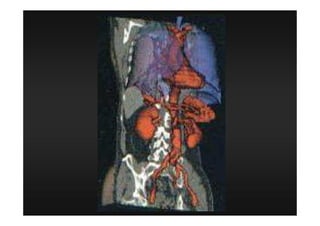

TOMOGRAFIA

COMPUTADORIZADA

Definição

É um método diagnóstico, no qual

são utilizados feixes colimadores,

muito finos, de Raios X, acoplados a

computadores que favoreçam

imagens detalhadas de seguimentos

corporais.

Procedimentos Especiais

3 D

MIP (angio)

MPR (2 D)

4 D

Todas as aquisições devem ter espessura

finas e incremento de 50 a 70 % da

espessura (quanto mais informação, mais

fidedigna será a reconstrução multiplanar)